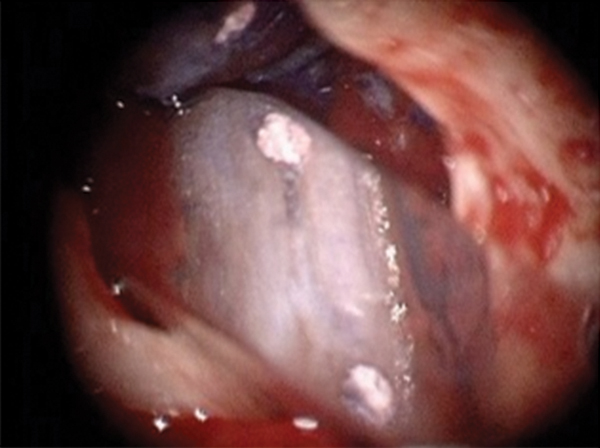

Figure 16. Post apicoectomy. Courtesy of Dr. Sam Kratchman.

Figure 16

Figure 17. Retropreps and isthus filled. Courtesy of Dr. Sam Kratchman.

Figure 17